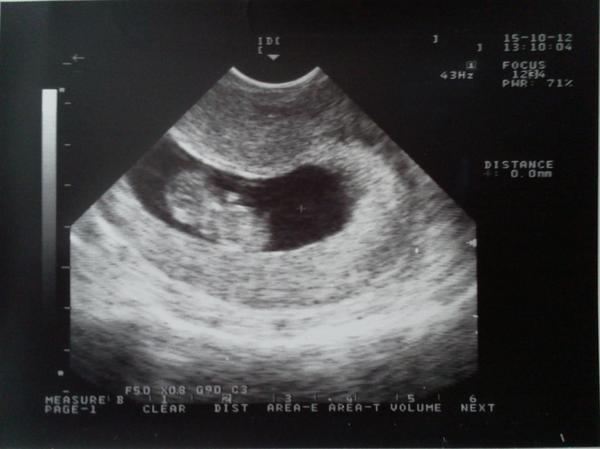

Ahoj holky, tak se hlásím z dnešní kotroly. Prcek je krásnej, zdravej, pěkně se tam hýbe 🙂

Ale je tada jedna novinka. Je tam asi ještě jedno! Dr. nejdříve myslela, že to dělá ten utz, jak s ním točí, protože zkusila i vrchní a tam viděla jen jedno. Pak zase spodní a viděla dvě a zase vrchní a to už něco viděla. Není si ale jistá. Pokud je tam i druhém tak je menší, říkala asi 14dní, ale srdíčko tam vidět bylo. Říkala, že buď je menší, může to být syndrom mizejícího dvojčete a přestane se vyvíjet nebo jsem měla 2 ovulace anebo je to prostě tím utz (má jen ten malý). Je prý dobře, že pokud jsou dvě, tak jsou každé zvlášť, kdyby něco, tak to druhé zůstane. Zajímavé ale je, že na kontrole před 14dny neviděla vůbec nic, ani tečku, váček apod. a teď je tam prcek. Na foto se jí oba nevešli a samotného menšího fotku nedělala, protože si nebyla jistá. Takže uvidíme asi až na genetice, co a jak. Máte s tím někdo zkušennost? Je to docela šok! Hlavně aby bylo všechno v pořádku!

Přidávám fotečku toho velkého prcka 🙂

Holky, tak jsme se nakonec napodruhé protlačily ještě do fakultky na utz. Dr. ukazovala, kde je mimčo, kde srdíčko a já se ptám, jestli je tam jen jedno a ona a proč by nebylo? a já že mojí dr. se zdálo, že jsou tam dvě, ale nebyla si jistá, no že ona tam vidí jen jedno, tak vrtěla tou sondou a ehle, fakt dvě. To druhé se jí zdá fakt menší nebo ten prostor tam má menší, ale nemohla ho změřit, protože tam leží jinak, ale má srdíčko. Nejlepší prej bude, když hned zavolám na ten screening, aby mě objednali co nejdříve. No holky, nevím co mám dělat. Mám strach, obavy, aby bylo vše v pořádku, ale taky jak bych všechno zvládla. Manžel nadšenej není. ☹ Nevíme ještě ani jak to je a řeší se peníze, malej byt atd. Možná to chce čas. 🙂